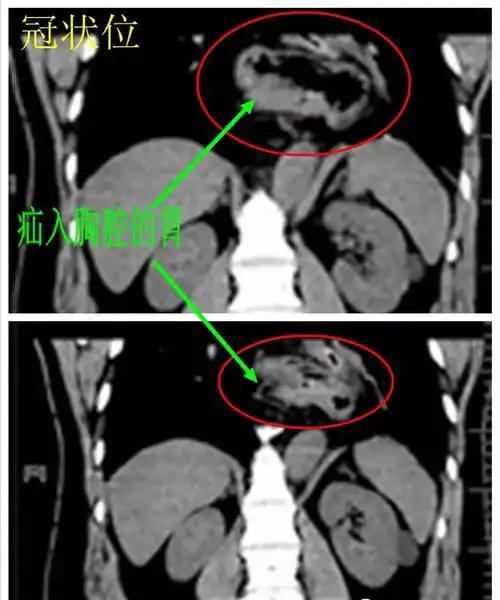

经典影像之食管裂孔疝 - 好大夫在线